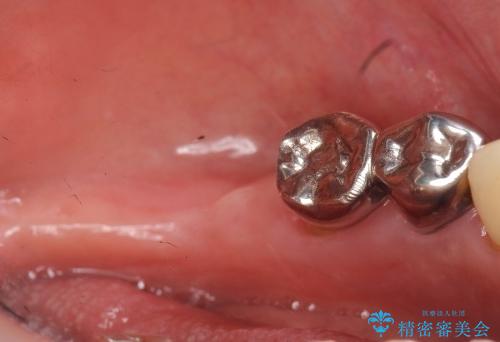

精査したところ、前歯の咬み合わせが反対になっていること、下の奥歯(下顎両側67)が4本欠損していることから動揺が生じていました。

下顎大臼歯が欠損したままで今ある歯に負担がかかりやすいことから、長期的予後は保証できないことをご理解頂いた上で治療を行いました。